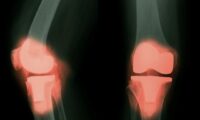

欠けた歯を速やかに補填しないと、歯並びの乱れや歯周病、不適切な咬み合わせなど、深刻な歯科的問題を引き起こす可能性があります。番組「She Health」のエピソードでは、台湾歯科インプラント協会連盟の専門家である李佳君氏が、さまざまな歯の修復方法について解説しました。

成人の場合、欠けた歯を補填しないと、隣接する歯が空いたスペースに倒れ込んでくることがあります。また、下顎の歯が欠けたまま放置されると、対になる上顎の歯が下方に伸び、不自然な咬み合わせにつながることがあります。これにより、歯の破折や過剰な摩耗、清掃が難しい部位が生じ、歯周病のリスクも高まります。

横断研究により、歯の喪失が顔の骨構造の変化と関連していることが示されています。前歯が長期間欠けていると、顔の非対称が生じる可能性があると、台湾歯科インプラント協会連盟の李佳君氏は指摘しています。